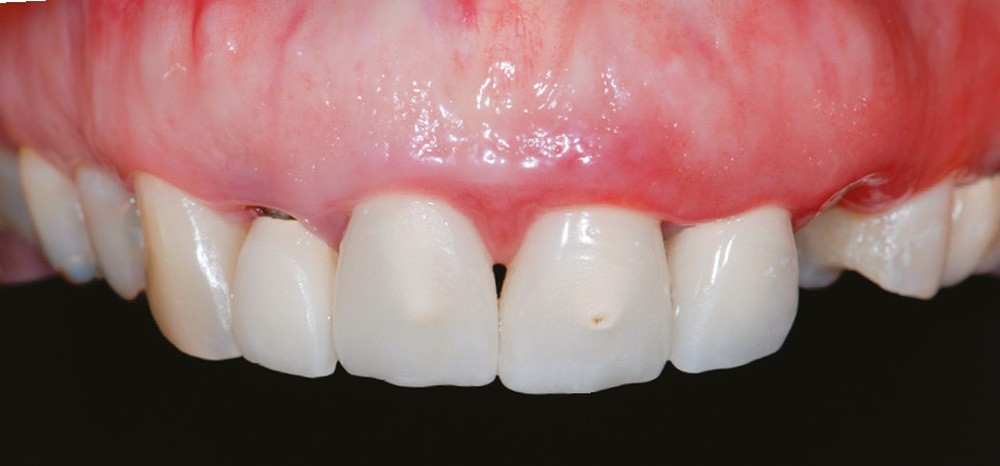

Même en l’absence de restauration, l’espace biologique n’est parfois naturellement pas correctement établi sur la dent. Ce phénomène est couramment décrit comme une éruption passive retardée. Elle peut être une indication d’élongation coronaire esthétique afin de rétablir la couronne clinique dans son intégralité (fig. 2a-c).

2 – L’élongation coronaire se fera aux dépens du parodonte superficiel et du parodonte profond. Une gingivectomie n’est possible que si le parodonte comporte plus de 3 mm de gencive kératinisée. En effet, il est recommandé…